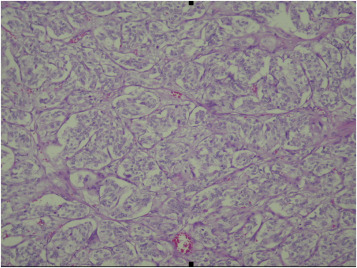

A 64-year-old woman with past medical history significant for hypertension had visited the emergency department many times over the course of several years due to intermittent hypertensive emergencies. On this presentation, she was admitted with features of symptomatic cholelithiasis. Abdominal ultrasound confirmed the presence gallstones and incidentally showed a 1.5-cm hypoechoic mass in the uncinate process of the pancreas (Figure 1 ). A physical examination was unremarkable except for mild right upper quadrant tenderness and elevated blood pressure (211/112 mmHg). Serum carcinoembryonic antigen and carbohydrate antigen 19-9 levels were both within normal limits. Contrast-enhanced computer tomography showed a 1.6-cm enhancing mass in the uncinate process of the pancreas (Figure 2 ). On magnetic resonance imaging, the lesion was identified as a 1.6-cm low-intensity mass on T1-weighted imaging and a slightly high-intensity mass on T2-weighted imaging. Magnetic resonance imaging with contrast enhancement revealed that the lesion was enhanced (Figure 3 ). On the basis of these findings, preoperative diagnosis was a pancreatic hypervascular tumor, suspected to be a neuroendocrine tumor. A pylorus-sparing Whipple procedure was recommended to achieve complete excision of the tumor and to treat the symptomatic cholelithiasis. Grossly, an oval and well encapsulated tumor measuring 1.5 cm in greatest dimension was noted within the lower part of uncinate process. Microscopically, this well-encapsulated tumor was composed of proliferation of polygonal cells arranged in trabecular, nest, and alveolar patterns separated by a stroma rich in vascular network. The tumor cells had an amphophilic-to-basophilic cytoplasm. Tumor nuclei were round to oval with moderate nuclear pleomorphism and prominent nucleoli (Figure 4 ). Mitotic figures were not identified. Capsular and vascular invasion was not present. By immunohistochemical staining, the tumor cells were reactive to CD 56, synaptophysin, and chromogranin A. The sustentacular cells surrounding the tumor clusters were also highlighted by immunostaining for S100. The lymph nodes dissected were free of malignancy. Both histomorphology and immunoprofiles of the tumor were typical of paraganglioma. Hypertensive urgency developed after the operation which was controlled with continuous intravenous nicardipine. Collected 24-h urine catecholamine data showed that norepinephrine levels were 175 μg/day (normal value: <97 μg/day) and vanillylmandelic acid levels were 8.06 mg/day (normal value: 1–7.5 mg/day). After 7-day nicardipine treatment, we gradually shifted to oral antihypertensive agents. Finally, the patient was successfully discharged with oral doxazosin (4 mg) one tablet per day. The patient had no clinical signs, symptoms, or family history suggestive of multiple endocrine neoplasia or Von Hippel–Lindau disease.

Figure 4. Tumor was composed of polygonal cells arranged in characteristic nested pattern “Zellballen.” Cytoplasm was amphophilic to basophilic. |